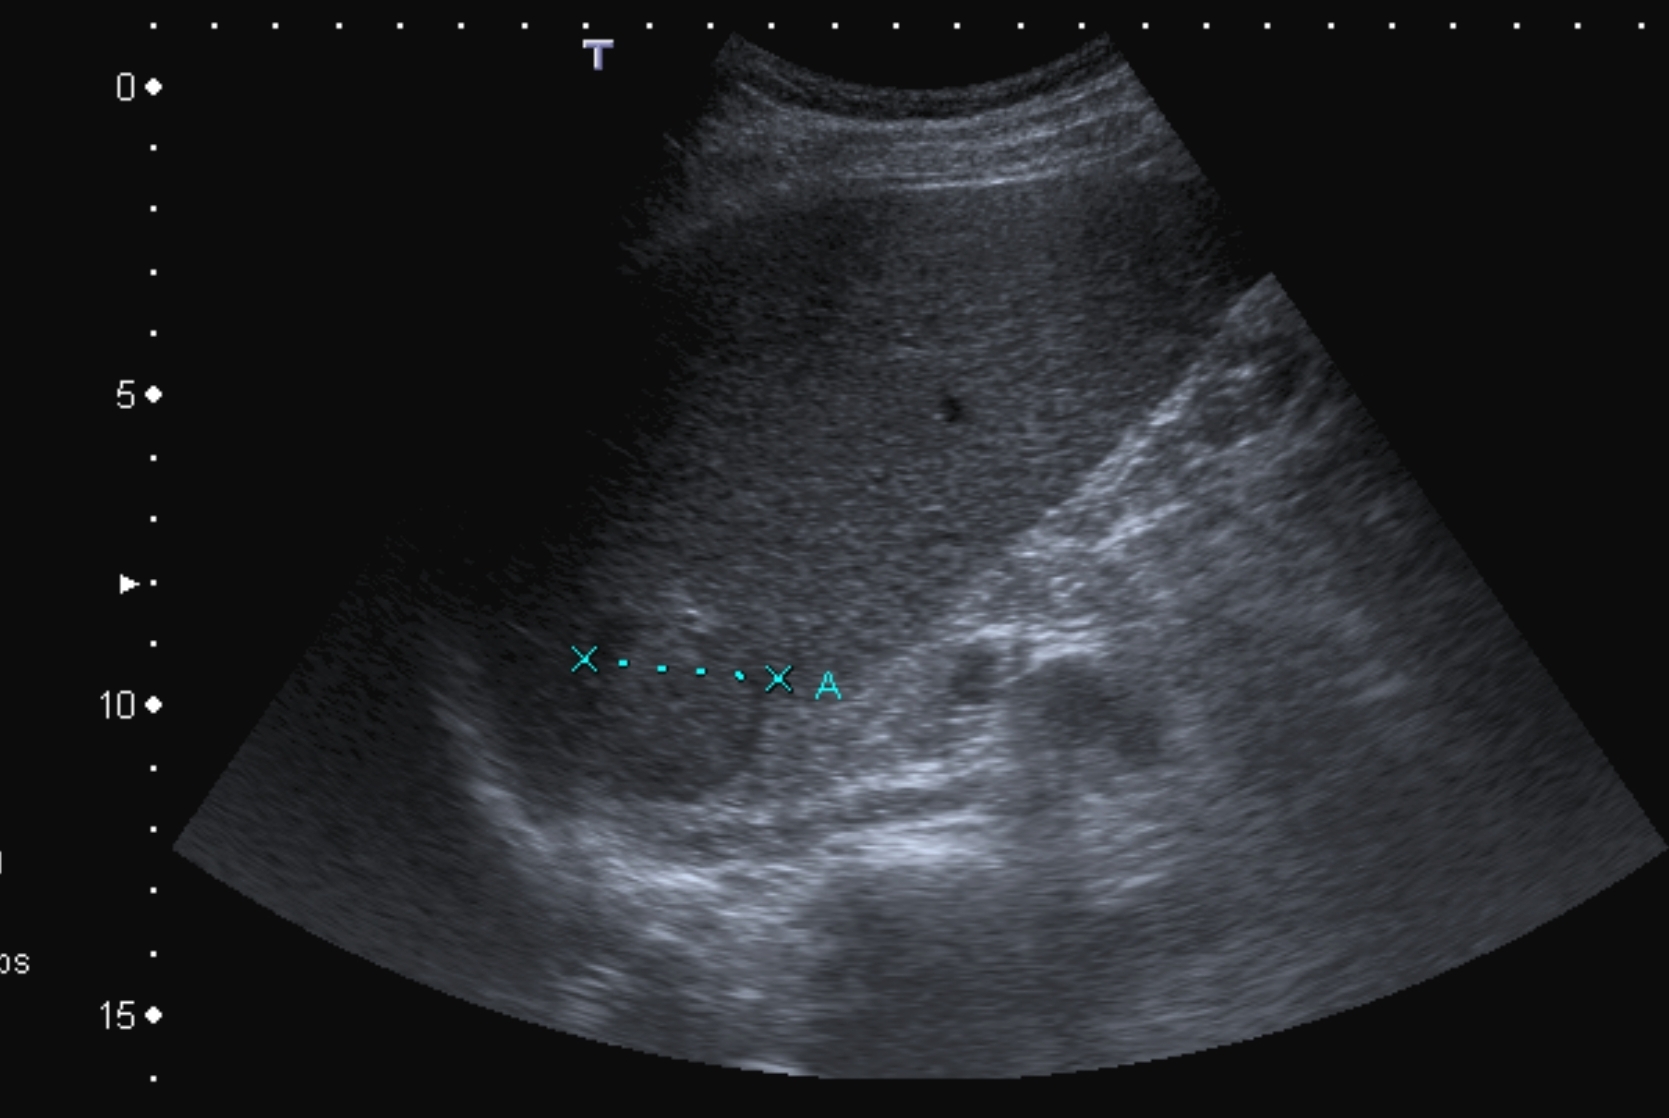

Their US apperarences include mostly an inhomogeneous, hyperechoic or hypoechoic lesion, which is arterially hypervascularised, and several arterioportal shunts may develop. The demonstration of shunt related portal vein flow disturbance by doppler US has a prominent importance. The adjudication of the cirrhosis related HCC by ultrasound is often a particularly difficult task.

Concerning the HCC, the knowledge of history is very important for the decision and usually the oncoteams consider the performance of an imaging modality guided biopsy basically important for the further therapeutic decisions (because of the hystological validation rather core biopsy should be performed! (Figure 26, 27, 28).

Figure 26: HCC, verified with FNAB, US